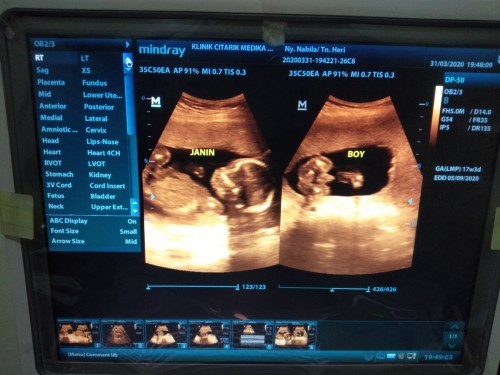

Saya 16 Minggu udah keliatan jenis kelamin nya (saat USG 4D)

16 weeks kalo saya. tergantung lagi dri posisi dedeknya bun

Kalo pas aku Usia 19minggu udh keliatan, USG 4D

tergantung posisi janin, aku dr 17wk udabh keliatan bun

aku lagi 18w udh USG kliatn jenis kelamin nya bun